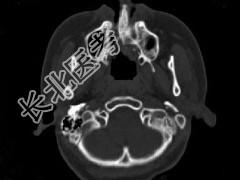

- 单项选择题男,14岁, 脓涕,头痛, CT检查如图,最可能的诊断是 ( )

A、右上颌窦炎

B、腭裂,右上颌窦炎

C、颅面骨发育不良

D、上颌骨骨结核合并瘘道形成

E、上颌骨骨脓肿并瘘道形成